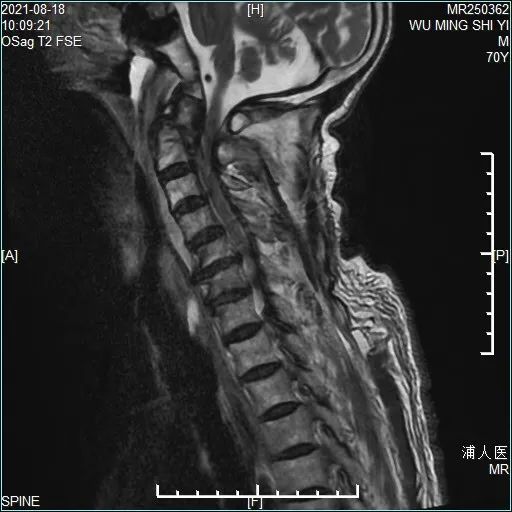

术前椎动脉CTA未见椎动脉高跨表现手术方法主要以前路齿状突螺钉加压内固定术和后路内固定手术为主:前路齿状突螺钉加压内固定术相对安全,但螺钉固定强度及复位能力不足;后路内固定手术方式相对安全的有椎板夹内固定、钢丝内固定等,但同样固定强度不佳,骨折端不融合发生几率高,枕颈融合术相对固定强度较大,但颈椎活动度受到限制,患者远期效果并不理想。为让患者术后保留更多的颈椎活动范围,手术团队放弃了风险相对较低的枕-颈融合术,而采用手术技术要求极高的寰-枢椎椎弓根钉内固定手术。在决定了治疗方案后,脊柱外科团队对患者进行了一系列术前准备工作,包括颈椎MRI检查、椎动脉CTA明确有无椎动脉解剖变异等。

术后颈椎MRI显示C1-2椎管内容积恢复,颈椎生理弧度恢复满意。在伤后1周由骨科王健主任主刀为患者成功实施了C1-2椎弓根钉内固定手术。术中O-arm成像同步计算机数字导航技术确保了椎弓根螺钉植入的精确性,缜密的术前计划和娴熟的手术技术保证了手术的顺利实施。整个手术过程中患者生命体征平稳,术后即刻解除了繁重的颅骨牵引,使用方便拆装的颈托辅助外固定。目前患者正处于术后恢复期,病情平稳,并在康复医师专业指导下进行康复训练。